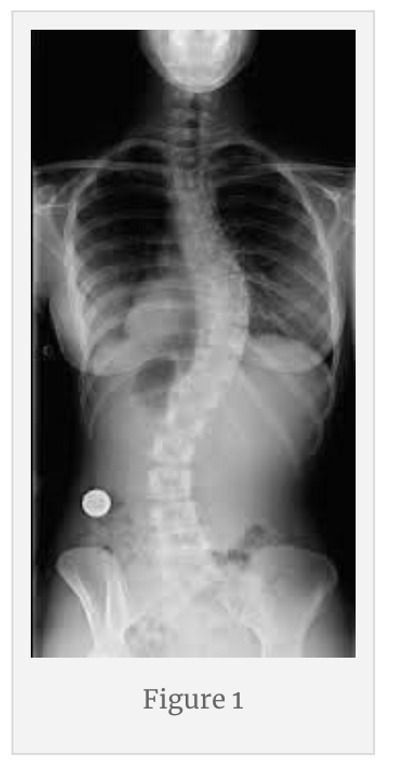

Restoring the human frame to Orthogonal and Tensegral has become quite the task. For over a hundred years chiropractic was the only…